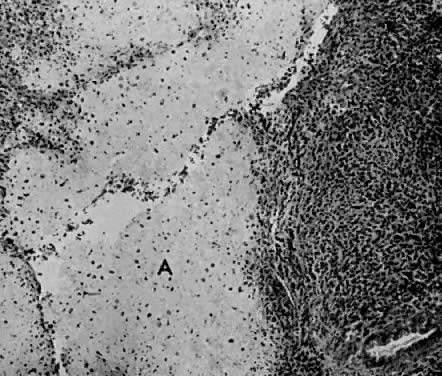

Microscopic.

In 1900, Wilms described the microscopic details of this tumor.6 Sarcoma botryoides is usually an embryonal rhabdomyosarcoma but may contain any or all three histologic types (alveolar, pleomorphic, or embryonal). The following microscopic features are characteristic: an overlying epithelium, a subepithelial cambium layer, round and spindle-shaped cells, and central myxomatous stroma.61

These tumors originate in the subepithelial tissue of the vagina. As they grow into the vaginal cavity, the polyps retain the original vaginal squamous epithelial covering (Fig. 12).

Fig. 12. Sarcoma botryoides arising from the vagina of a 2-year-old girl, showing the squamous epithelium ( A) and the subepithelial cambium zone ( B ). Notice the central myxoid loose stroma ( C) (× 360)

Immediately beneath the covering epithelium is the cambium layer. This layer is composed of round and spindle-shaped cells closely packed together. The typical rhabdomyoblast may be visible here. The rhabdomyoblast is an immature malignant cell that resembles striated muscle cells in different phases of development: round, racket, or straplike forms.61,65,66 The cytoplasm is eosinophilic and granular. Cross-striations can be readily demonstrated with the use of a phosphotungstic acid-hematoxylin stain (PTAH).

The central portion of the polyps is relatively acellular (see Fig. 12) and is composed mainly of myxomatous tissue, but a few spindle- or stellate-shaped cells may be visible.